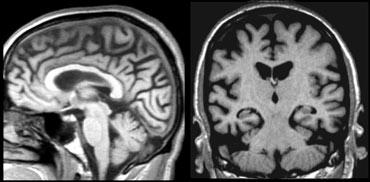

Chuỗi xung T1W mặt phẳng coronal qua hồi hải mã cho thấy teo não tiến triển trong AD gia đình (hình ảnh được cung cấp bởi Nick Fox).

Nếu có nghi ngờ mạnh về bệnh Alzheimer, việc lặp lại khảo sát có thể hữu ích để theo dõi sự tiến triển của tình trạng teo não (thùy thái dương giữa).

Các hình ảnh cho thấy kết quả theo dõi tại thời điểm 18 và 36 tháng ở một bệnh nhân có nguy cơ mắc AD gia đình, minh họa sự tiến triển của bệnh.